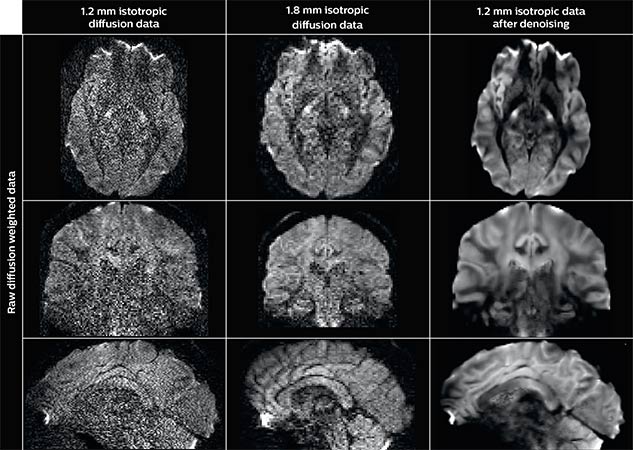

Using a non-local spatial and angular block matching technique to denoise raw diffusion weighted images. allows to push acquisition to lower spatial resolution and read human-connectome-project-like resolution from standard Philips Ingenia 3.0T MRI scanner.

The data were acquired with spatial resolution of 1.2 x 1.2 x 1.2 mm in 13 minutes for 40 full brain DWI with b 1000 and one with b 0